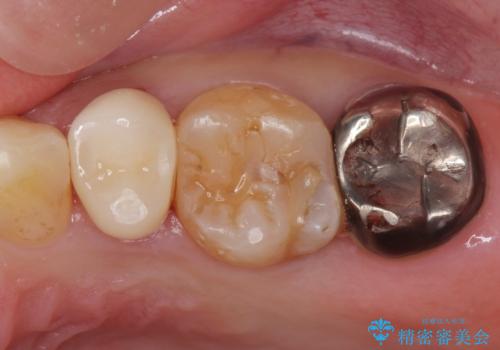

- 他院で被せた保険の白い被せ物(樹脂)をセラミックの被せ物に変えたいとの事で来院。

被せ物を外し、虫歯がないことを確認してセラミックの被せ物(ジルコニアクラウン)の治療を行いました。

白くて適合の良い被せ物が入りました。

セラミックは劣化することがなく虫歯の再発のリスクが低くなります。